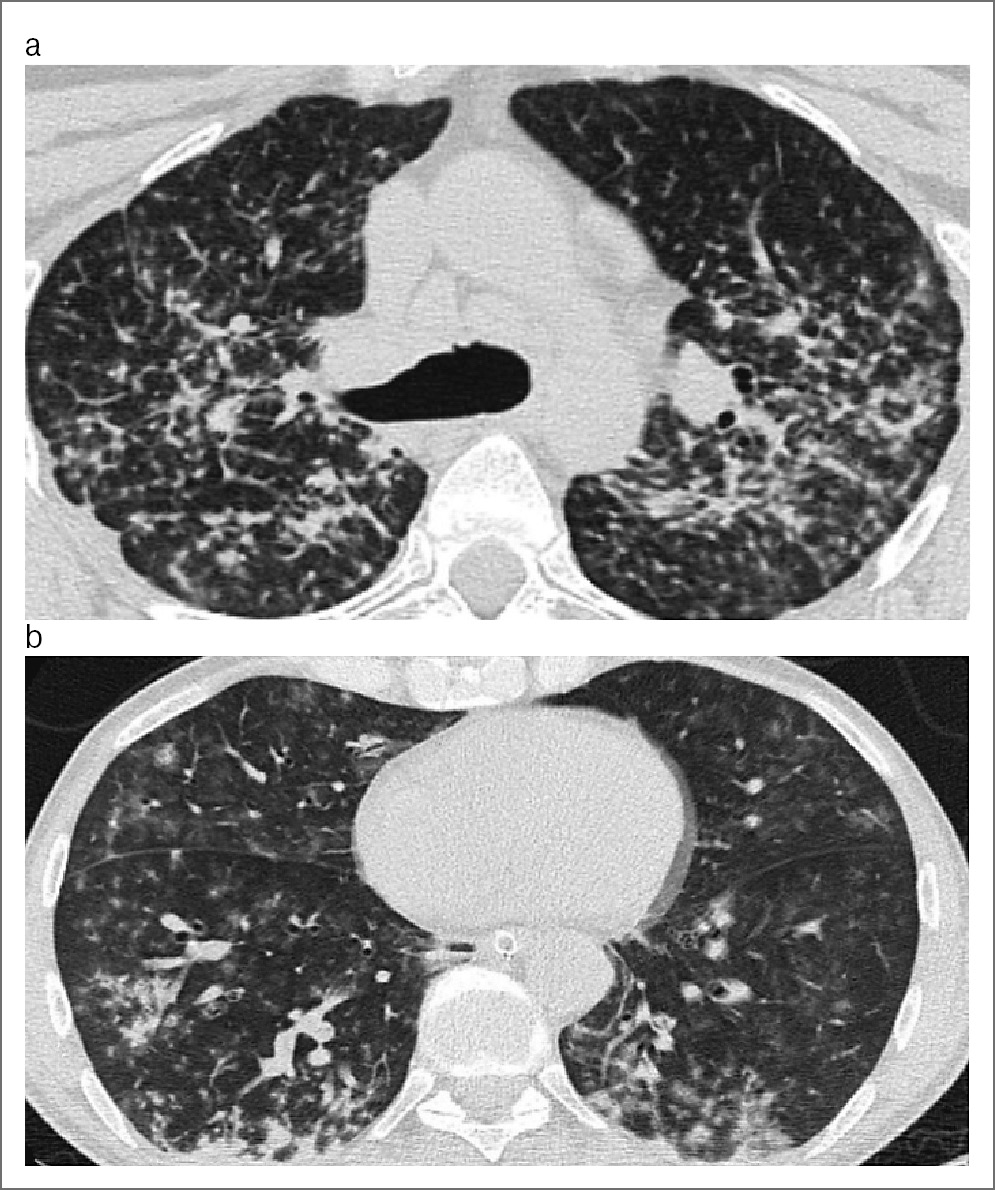

В качестве примеров приводим снимки КТ органов грудной клетки у больных IVВ стадией ВИЧ-инфекции с ИД в фазе прогрессирования и при отсутствии АРВТ, иллюстрирующие сходство визуализации патологических изменений в 1а и 1б группах (рис. 1, a, b) и в 2а и 2б группах (рис. 2, a, b).

Рис. 1. КТ органов грудной клетки. Аксиальная проекция, режим легочного окна: a – пациент, возраст 32 года, с IVB стадией ВИЧ-инфекции с ИД в фазе прогрессирования, без АРВТ и с верифицированной коморбидностью ТОД, ГВП и КВП; b – пациент, возраст 29 лет, с IVB стадией ВИЧ-инфекции с ИД в фазе прогрессирования, без АРВТ и с верифицированной коморбидностью ТОД и ГВП.

Как видно на рис. 1 и 2, на снимках КТ органов грудной клетки визуализируются однотипные 4 синдрома: диссеминации, патологии плевры усиления и деформации легочного рисунка с участками «матового стекла» и аденопатии.